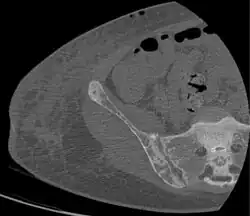

Subchondral resorption in the sacroiliac joint.[18] -